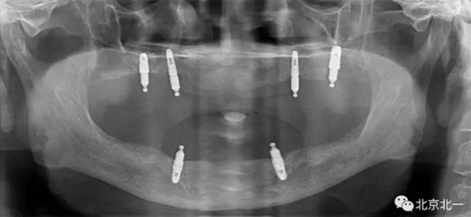

圖二:覆蓋義齒

2.png